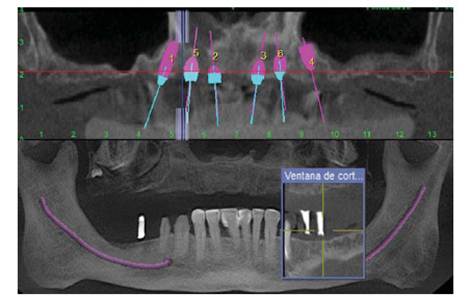

Luego de 6 meses se procedió a reevaluar el caso (2da fase), realizar el protocolo reverso y observar las condiciones tomográficas de los tejidos remanentes, durante todo este tiempo el paciente fue citado en la especialidad de Periodoncia para mantener los tejidos periodontales y un IHO óptimo.

De acuerdo al protocolo reverso y al examen tomo-gráfico (Figura 2) con las guías multifuncionales mantuvimos la planificación inicial de realizar una prótesis híbrida superior implanto soportada sobre 6 implantes y 3 implantes en el maxilar inferior (Figura 3 ),

El uso de implantes dentales como forma de retención para prótesis representa una opción de tratamiento previsible para la rehabilitación de pacientes edéntulos totales y parciales (12. De acuerdo al protocolo reverso y a la toma tomográfica decidimos una prótesis hibrida superior sobre 6 implantes, siendo los distales inclinados para disminuir la distancia AP y disminuir la sobrecarga 13. Esta prótesis híbrida consta de una estructura metálica que se asienta pasivamente sobre los mini pilares 14,15, y una estructura de acrílico con dientes sobre ella, con una alta tasa de supervivencia (93,3-100%) 16.